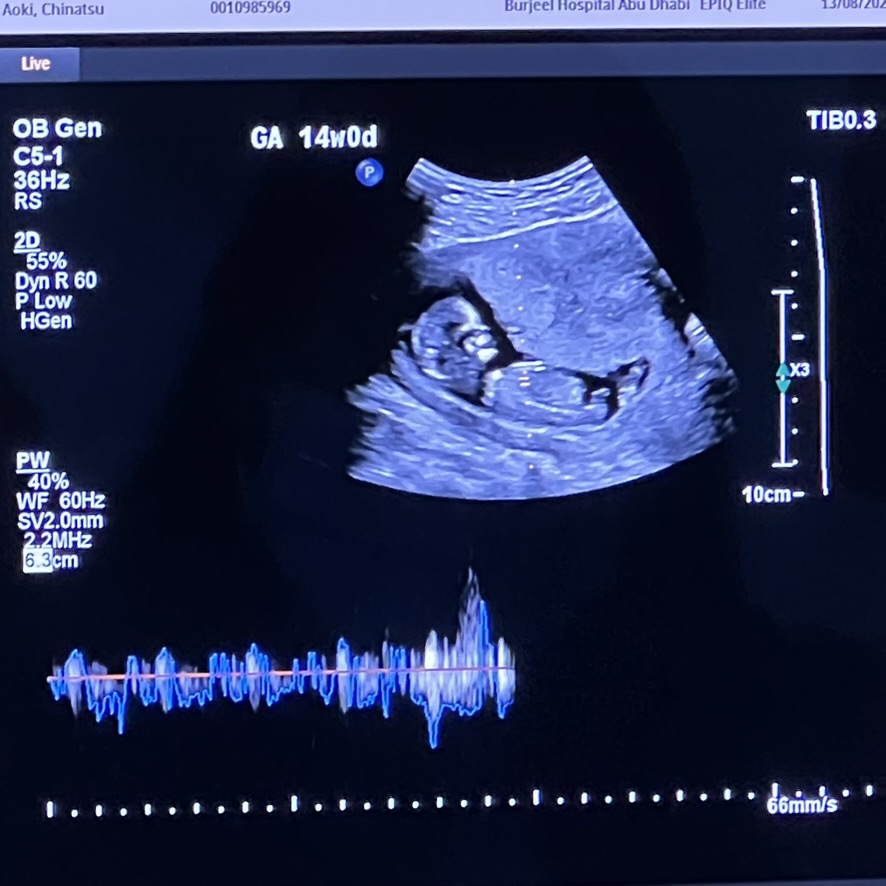

The baby continues to grow and continues to stay a baby! We learn it's a boy and we quickly decided to name him Thomas. Do not ask me what Neo's first name is. And do not insinuate a relation because it's definitely not related at all. Haha. (it is)